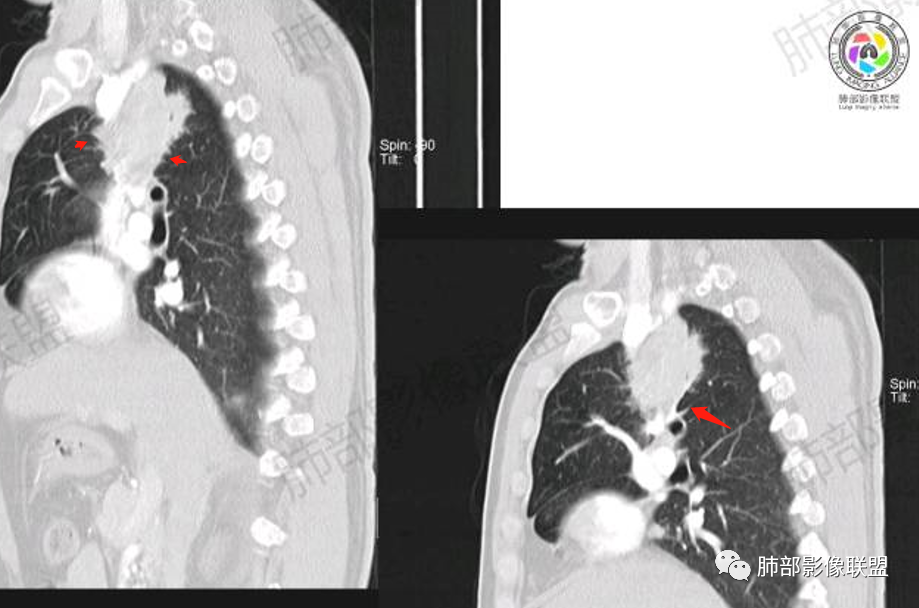

胸部CT:

MALT淋巴瘤影像表现为实变、结节及磨玻璃影,其中实变是其特点,胸膜下或支气管血管束节段性分布具有特征性,跨叶征较常见,这可能与肿瘤细胞进入血循环后往往又回到上皮黏膜部位,它们从一处黏膜到另一处黏膜,但不会到外周淋巴组织等有关。国外多名学者的影像-病理研究报道认为其病理学基础是由于肿瘤细胞沿支气管血管束周围间质及胸膜浸润生长,形成小叶间隔增厚、支气管血管束增粗等间质性改变,进一步浸润肺泡壁、充填肺泡腔。

①实变的出现率100%,多表现为两(89%)或单肺多发,密度均匀,与邻近胸壁肌肉的密度大致相等,少见钙化(15%),这与病灶内血管保持 完整,血供丰富,且肿瘤生长缓慢,对缺氧耐受好,不易坏死有关。边缘磨玻璃影或晕征具有特异性,其病理学基础是肿瘤细胞对小叶间隔、肺泡壁的淋巴瘤样浸润;

③扩张的充气支气管为其较特征性的表现,出现率约为89%,支气管管壁无破坏,支气管常扩张并达病灶的边缘,这与炎症性肺癌明显不同,其病理学基础是肿瘤起源于肺间质,肿瘤细胞沿着脏器解剖结构生长,周围增生的结缔组织牵拉导致支气管扩张,因而这类支气管扩张在肿瘤治疗后有时可消失;

④血管造影征是另一 点,强化的肺血管形态及走行正常,无扭曲或增 粗,其病理学基础为肿瘤细胞沿间质增生浸润,不破坏血管或支气管,病灶内肺支架结构完整,本研究发现率为75%;

⑧邻近胸膜多无增厚,部分胸膜下见清晰脂肪或少许积液可能具有一定特征性,既往国内外研究尚未报道此征象,本文认为其病理学基础可能为肿瘤细胞生长缓慢,多为间质淋巴瘤样浸润而不破坏脏器解剖结构,肺泡塌陷及周围纤维组织增生,可能致病灶牵拉邻近胸膜有关,这不同于文献;报道的机化性肺炎致邻近胸膜多条状水肿、增厚,此征象有助于二者的鉴别。